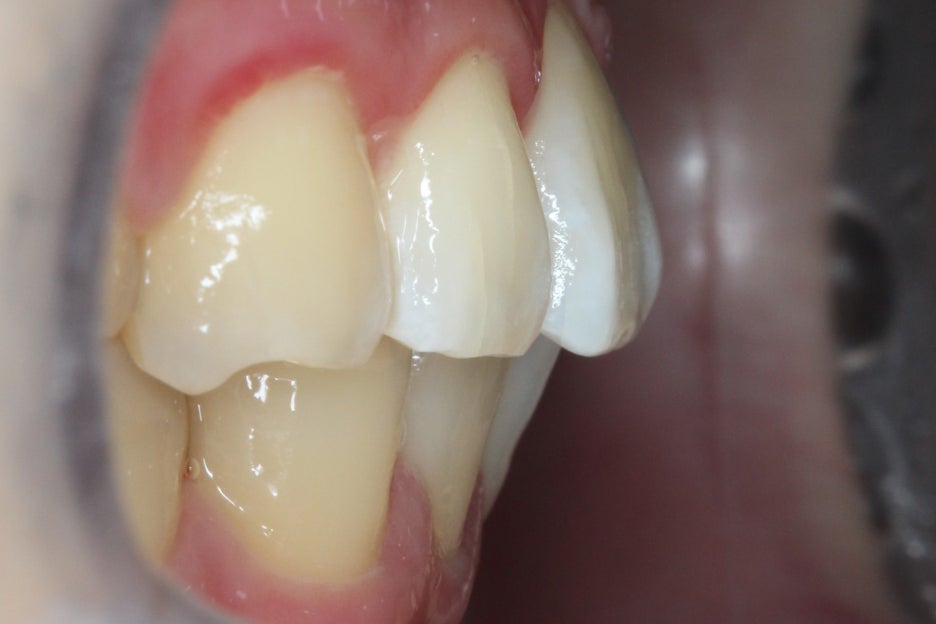

측면에서 overjet을 보면 중절치의

돌출 증상이 심한 모습으로 상악이

전방으로 뻐드러져 있어 입이 튀어나와 보이고

자꾸 입이 벌어지는 습관이 생길 수 있습니다.

이러한 경우 돌출된 앞니나 전치부를

교정하여 돌출감을 완화할 수 있어요.

2mm를 넘을 경우 돌출이 있다고 판단되기 때문에

치아를 교정하는 것이 좋습니다.